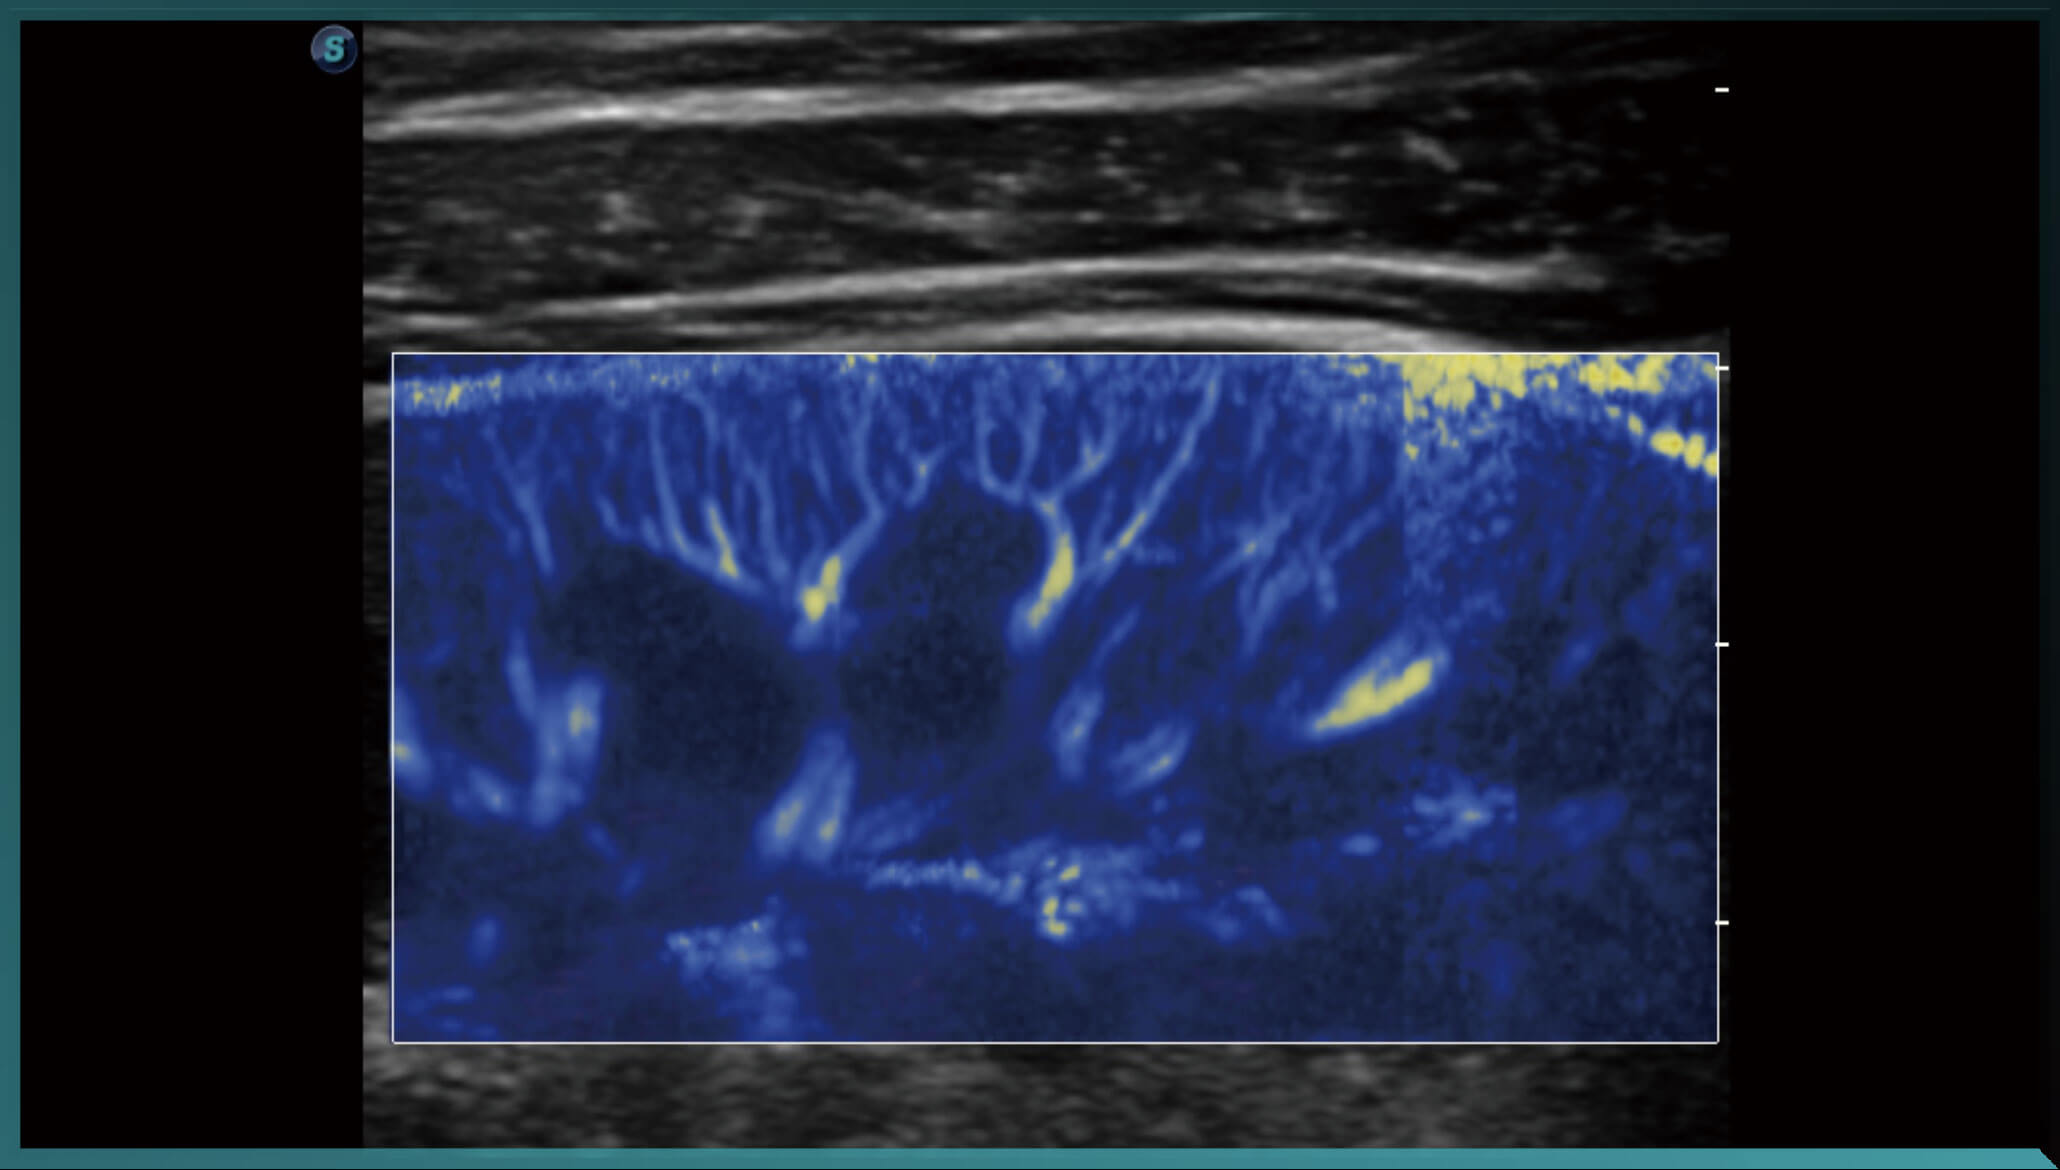

Micro F ( siêu âm vi mạch)

Micro F cung cấp một phương pháp cải tiến để mở rộng phạm vi dòng chảy có thể nhìn thấy trong siêu âm, đặc biệt là để hình dung huyết động của các mạch máu nhỏ. Mang lại sự tự tin chẩn đoán cao hơn để đánh giá các tổn thương và khối u.